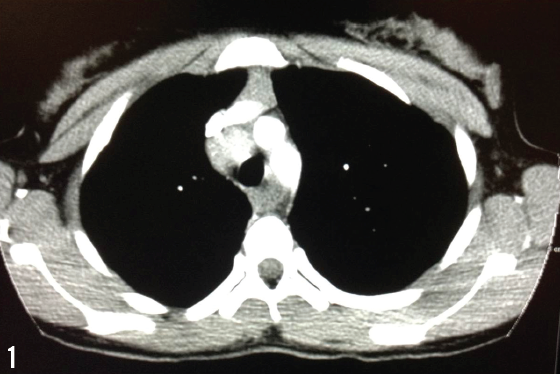

Roger Rossi, DO; Kathryn Eckert; Dawn Deike, DO; Chun Ho, MD

This article presents a case of severe DCM in a 15-year-old boy with DMD who presented clinically with gastrointestinal symptoms.

A boy aged 2 years and 9 months was admitted to a hospital’s pediatric unit with a chief concern of difficulty breathing, which had started a few weeks ago.